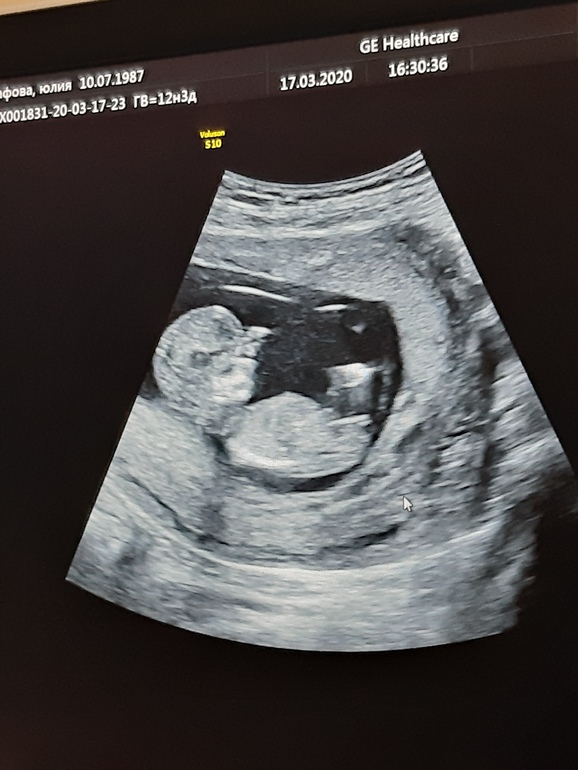

Там, где причинное место, торчит т.н. половой бугорок. Если он расположен более-менее параллельно позвоночнику (он хорошо проглядывается), то это девочка, а если угол бугорка к позвоночнику более 30°, то мальчик. У вас прям параллельно.

Но я не узист и не врач, это только моё мнение.

А как вы поняли? Просто чисто из любопытства)) я вот вижу вроде как голову и пузико, как тут пол разглядеть?)))

И я вот удивляюсь экспертам )). Между ножек когда делают обзор ..снизу и тогда видно ! А что здесь то видно?! Силуэт и очертания маленького человека только вижу! Пусть растёт и развивается правильно!

На первый взгляд - девочка. И если допустить,. Что в районе паха - это визуализируется половой бугорок (что вообще не факт, по одной такой фотке сложно судить) то больше похоже на девочку, а мальчиков половой бугорок вверх торчит.